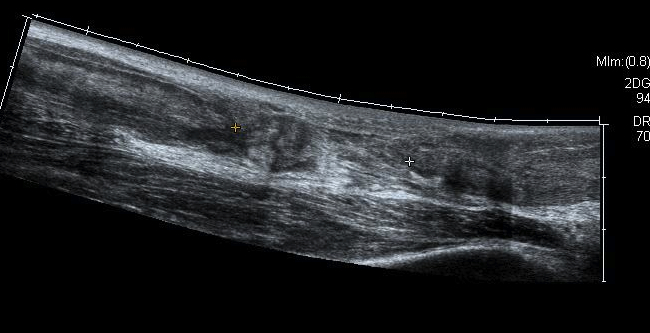

Ultrasound

Diagnose rupture and check reduction of tendon ends with plantarflexion

Aminlari et al J Emerg Med 2021

- systematic review

- ultrasound 95% sensitive and 99% specific for complete rupture